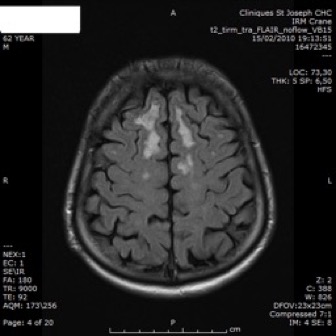

Axial FLAIR (A–C) and T2*GE (D)

- hypersignaux confluents (A–C)

- infarctus lacunaires (A, flèche)